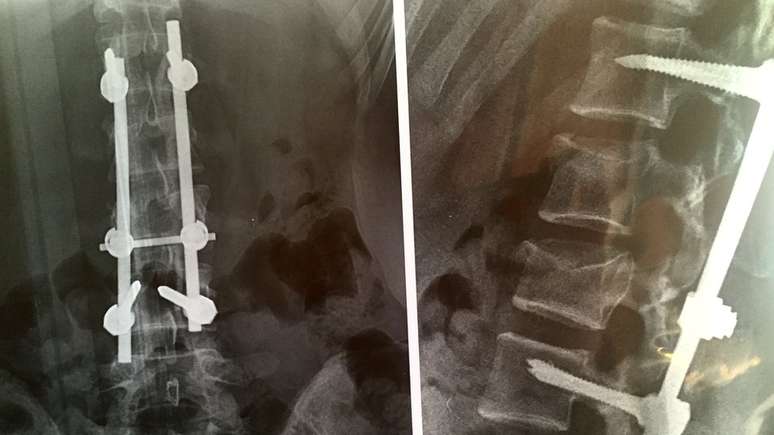

Raio-x da coluna vetebral de Maria With Hoen, mostrando implantes metálicos

Os companheiros de viagem, no entanto, encontraram a norueguesa em uma pequena borda, menos de 10m abaixo. Apesar do alívio, Maria tinha sofrido ferimentos graves: fraturas múltiplas na coluna obrigaram os médicos a correrem contra o tempo para que ela não ficasse paralisada.

Os médicos não sabiam se a jovem conseguiria se recuperar, apesar de terem reconstruído sua coluna com o auxílio de implantes metálicos.